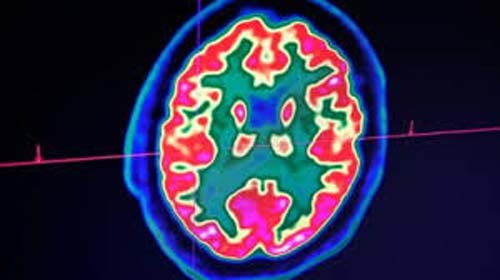

O coronavírus também pode afetar o cérebro

E um artigo do New England Journal of Medicine, a revista médica americana de maior prestígio, destaca que médicos franceses estudaram 58 pacientes com coronavírus e comprovaram que metade deles estavam desorientados ou agitados. Exames de imagens do cérebro mostraram possíveis inflamações.

Este paciente se mostrou desorientado, sofreu convulsões e o exame de imagem do cérebro revelou inflamações. Mas os cientistas preferem a cautela, pois trata-se de um único caso conhecido até o momento e que os exames para detectar o vírus no líquido cefalorraquidiano ainda não foram validados.